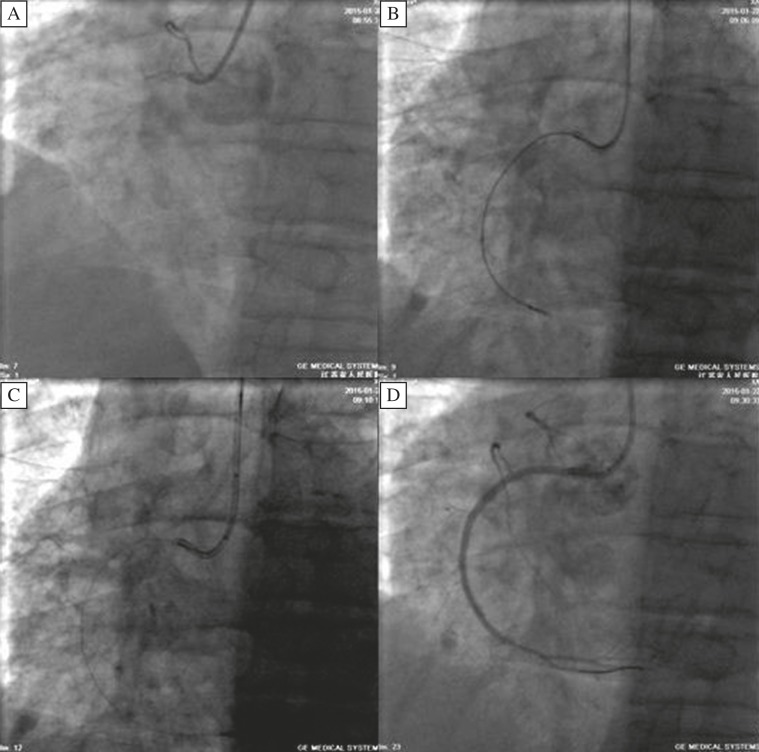

Fig. 2. Operation process of the patient performed with the new technique.

A: CAG showed completely obstruction in the proximal RCA. B: The microcatheter advanced into the distal part of the RCA through the CTO lesion. C: The microcatheter was withdrew within the guide catheter (at the end of the the ascending aorta). The balloon was dilated with 8–10atm when the predilation balloon was inserted 2–3cm distal the microcatheter to fix the guidewire at the inside wall of the guide catheter. The microcatheter was withdrawn slowly with no shifting of the guidewire. D: CAG after the operation showed no stenosis in the distal vessels of RCA and TIMI 3 flow.

Here we present a case which was performed with the new tchnique. A 84-year-old male patient was admitted to our hospital because of chest tightness for 8years. Conventional coronary angiography demonstrated approximately 60-70% stenosis in proximal-segment of left anterior descending artery (LAD), around 50% stenosis in proximal-segment of diagonal branch and around 90% stenosis in proximal-segment of OM2. Left circumflex artery (LCx):30% stenosis in proximal-segment and 60% stenosis in distal-segment. Coronary angiography showed a CTO of the proximal right coronary artery (RCA). No stenosis was found in LM. After seeking the concurrence of a relative, PCI for CTO of RCA was performed. SAL guiding catheter arrived at the RCA orifice with additional unfractionated heparin 8000u. FIELD XT gained access to the distal-segment through the occluded part under the guidance of the microcatheter, withdrew the microcatheter, Stent implantation was successfully performed using a 2.5*32mm and 2.75*38mm TAXUS stent from the distal to the proximal part following PTCA, followed by post-balloon dilatation. A Runthrough NS guide wire was advanced at the diatal part through the lesion. A 2.25*18mm ENDEAVOR stent was successfully implanted at the lesion after a 2.0*15mm SPRINTER balloon predialation. The operation was successful and the patient returned to the ward safely.